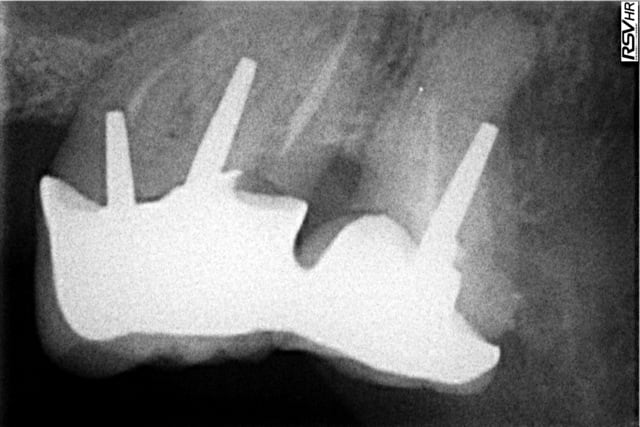

J'ai mis en lien la radiographie ainsi que la photographie d'un cas qui date d'aujourd'hui. Il s'agit de Monsieur qui vient sur les recommandations de Madame que je soigne. Il vient de se faire poser deux couronnes et ressent de vives douleurs à la mastication. RAS pour son ex dentiste.

Je reçois Monsieur, me fais bien confirmer que les prothèses viennent d'être posées. Je pose le diagnostic d'extraction (perforation plancher de la 7).

le tenon de la 8 , pas un peu long ?

Ne veux tu pas éssayer de traiter la perforation?